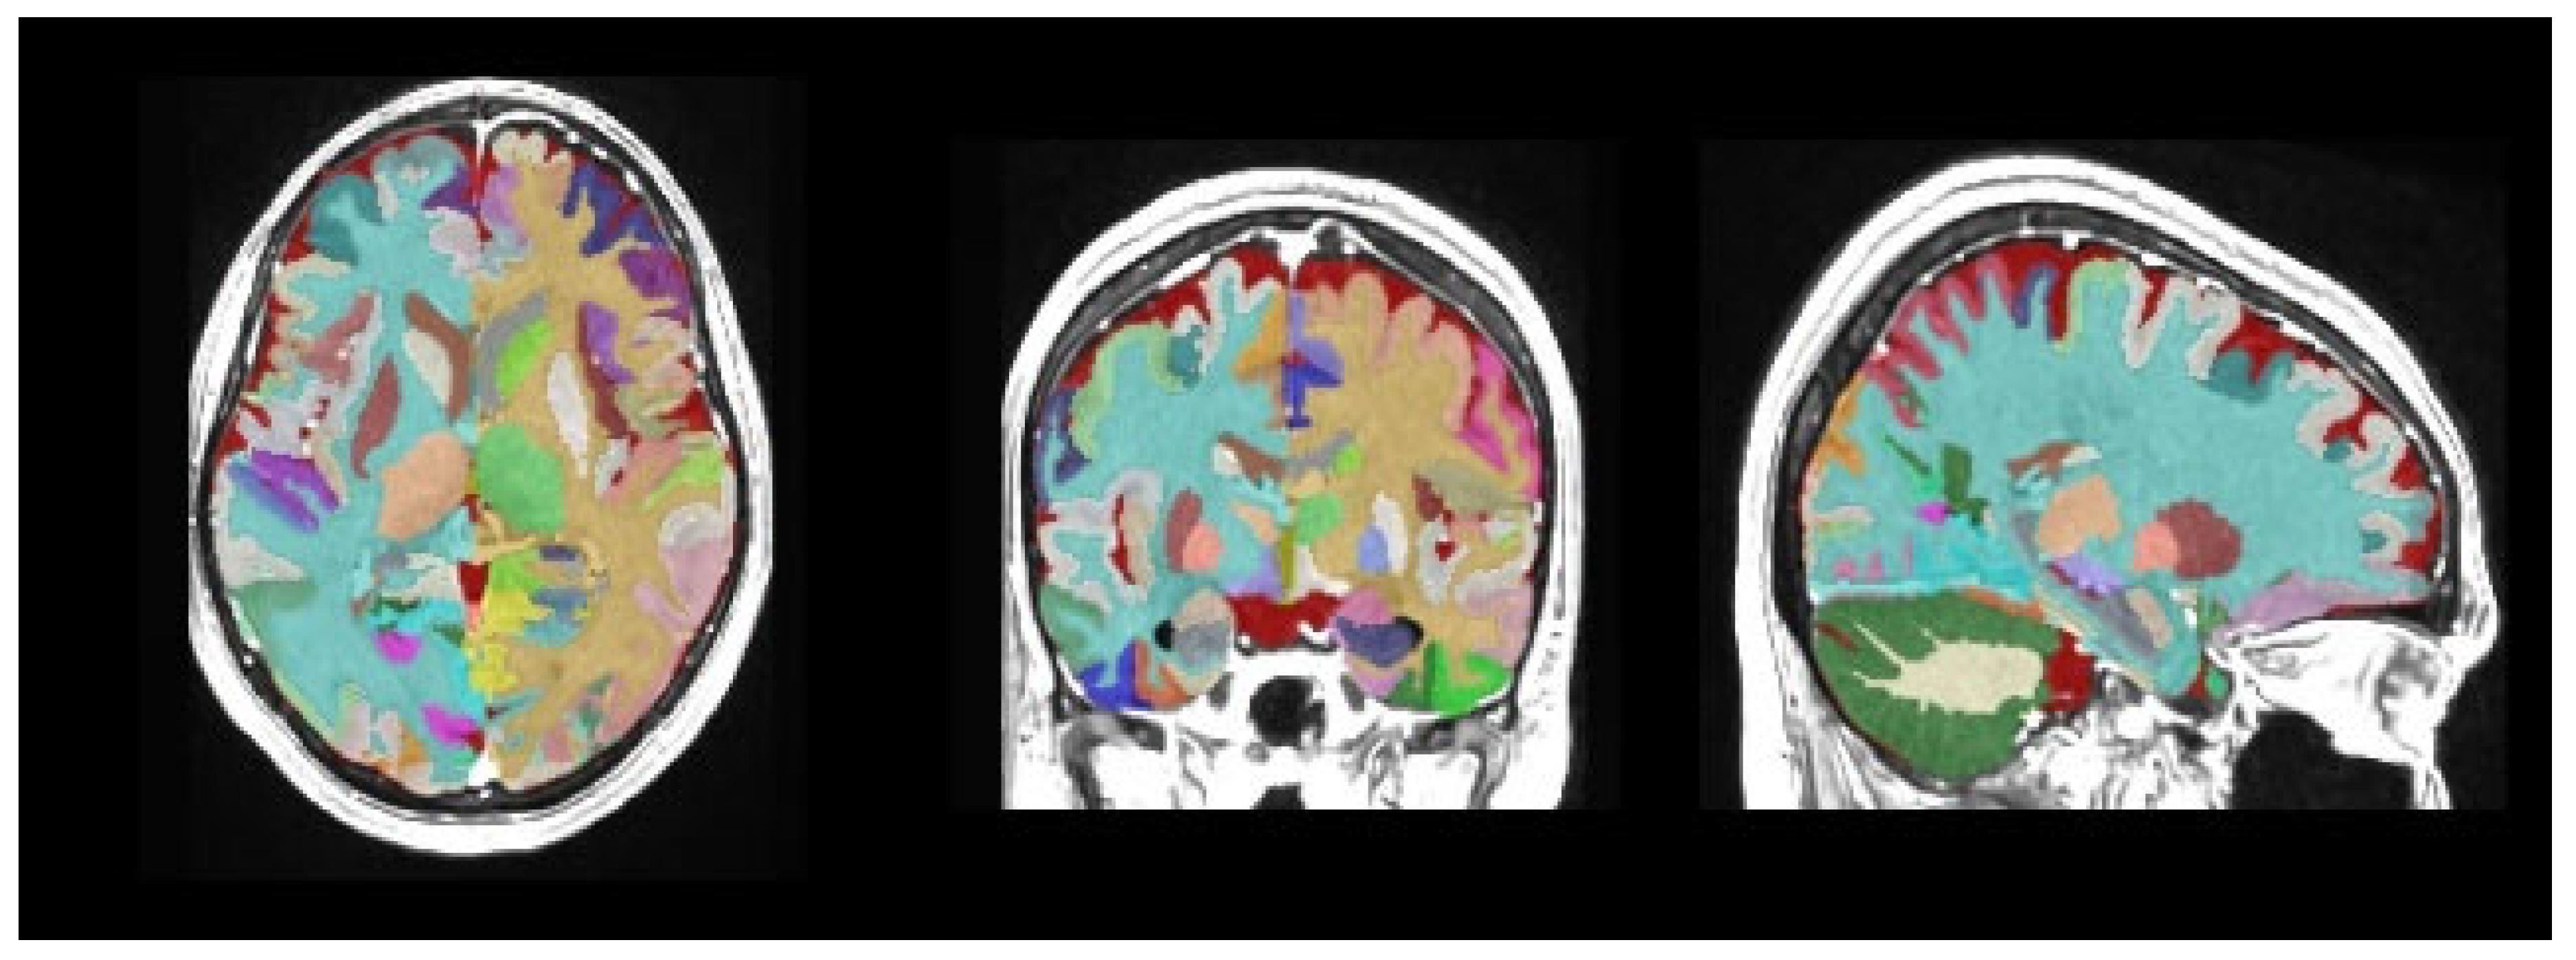

- Manjón, J.V.; Coupé, P. volBrain: An Online MRI Brain Volumetry System. Front. Neuroinform. 2016, 10, 30. [Google Scholar] [CrossRef]

- Soysal, H.; Acer, N.; Özdemir, M.; Eraslan, Ö. Volumetric measurements of the subcortical structures of healthy adult brains in the Turkish population. Folia Morphol. 2022, 81, 294–306. [Google Scholar] [CrossRef]